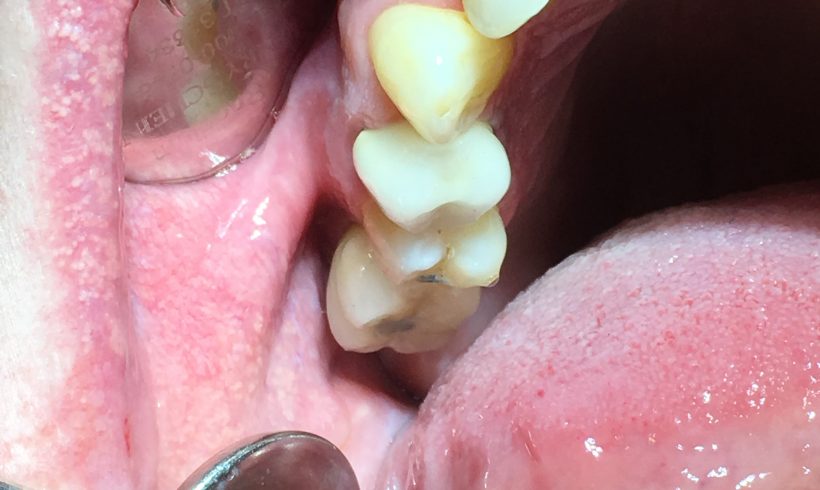

The crown is fixed to the osseo-integrated implant using a screw torqued into place. A white filling is then placed over the screw to protect it. Now The patient can function fully. We have increased the surface area upon which to chew food. The patient was delighted with the final look and feel.